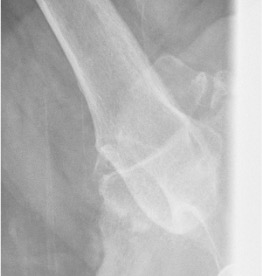

Xray

Signs of chronic shoulder dislocation